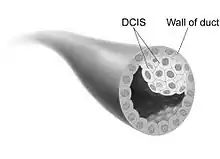

Breast ductal carcinoma

Ductal carcinoma in situ (DCIS) is the proliferation of malignant ductal cells without penetrating the stromal tissue around them.[12] In other words, DCIS is the presence of abnormal cells in a breast's milk duct. It is thought to be the earliest form of breast cancer and is noninvasive (it has not spread from the milk duct and has a low risk of becoming invasive).[13] DCIS can be differentiated into groups based on low, intermediate, and high grade. When comparing the growth potential of normal epithelial cells to DCIS, it is 10 times larger, and the apoptosis rate was also 15 times greater. Furthermore, comedo-type DCIS usually causes necrosis in the duct center and has a more significant threat of reappearance.[12]

The majority of ductal carcinomas are positive for luminal cell markers (CK8, CK18, CK19) but negative for basal cellmarkers (CK5/6 and CK14). In 30% of cases, DCIS is multifocal and usually is in the same breast. There is axillary lymph node invasion in 2-6% of DCIS cases. DCIS is frequently found during mammograms and makes up 25% of screen-detected breast cancers.[12]

The degree of the disease in the breast determines DCIS treatment. In widespread or multifocal DCIS patients, a mastectomy is the recommended choice with the chance of reconstruction.[13] Further clinical trials are being worked on to find an alternative to surgery.

There is not a clear cause for DCIS. This type of cancer comes from genetic mutations in the breast duct cells' DNA. The mutations make the cells look abnormal, but these cells are still not able to leave the breast duct. It is unknown what the exact cause is of this abnormal cell growth that causes DCIS. However, factors that potentially have a role are lifestyle, environment, and passed-down genes.[13]